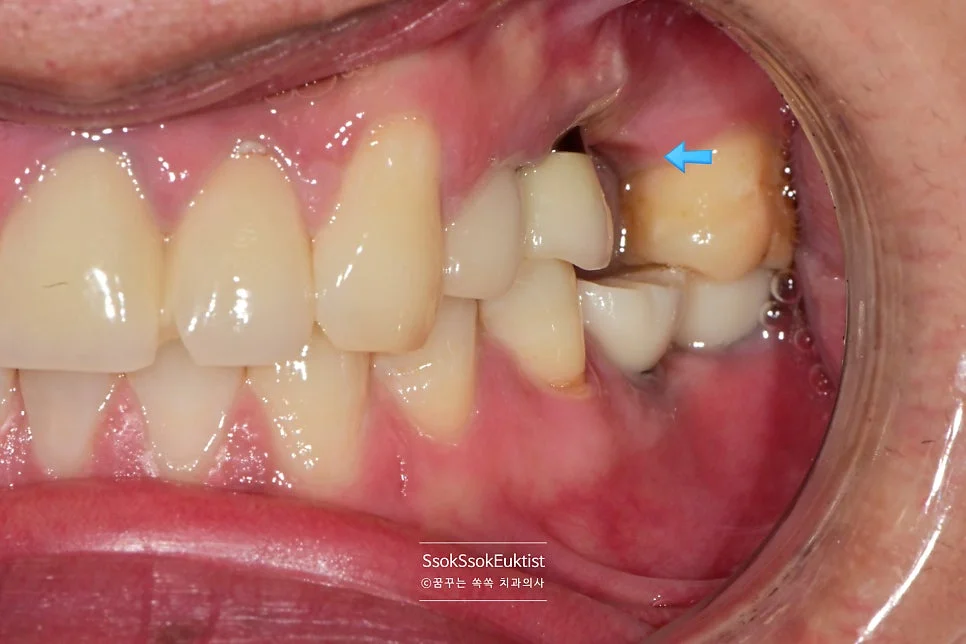

2nd 수면 마취 — 두 번째 수면 마취에서는 오른쪽에 세 개의 임플란트를 식립합니다.

단단하게 유착되어 있는 임플란트를 제거하고 바로 그 자리에 임플란트를 식립하는 고난도 시술인데요^^

2차 수면 마취 — 우측 임플란트 3개 식립 완료 (화살표)

가능한 주변 골보다 2~3mm 깊게 임플란트가 온전히 뼈 안에 잠기게 식립되었다면 잘 심긴 임플란트입니다.

오른쪽은 뼈이식이 많이 들어갔기에 3달의 치유 기간을 가집니다.